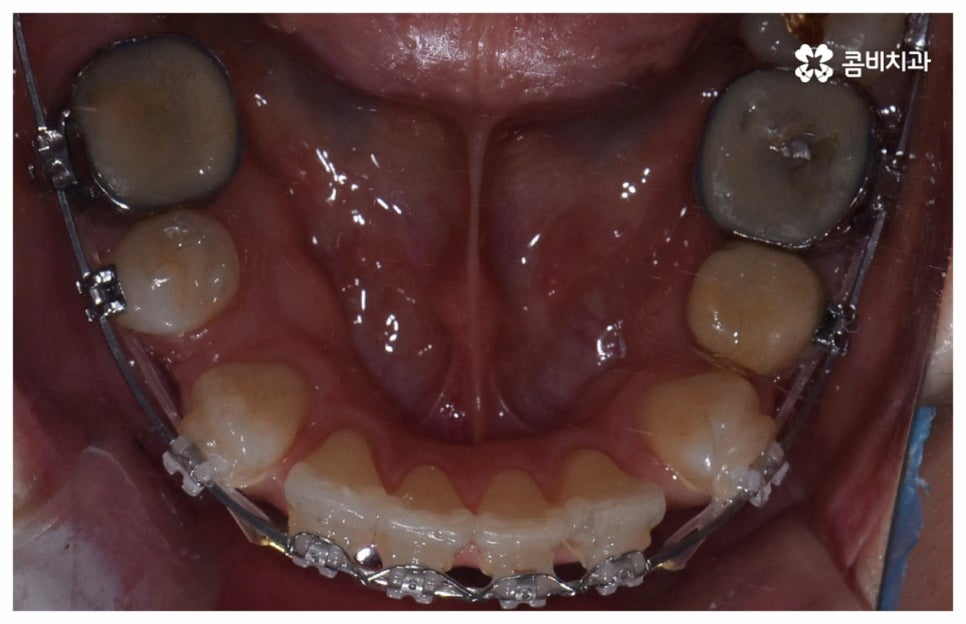

위 사진은 환자분의 동의를 받아 이해를 돕기 위한

사진이며, 실제 치료 결과는 다를 수 있습니다.